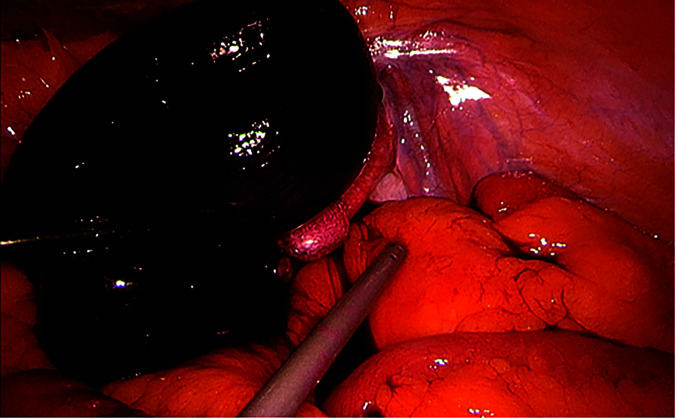

Presentation of the case: We report a case of 74-year-old male patient who presented with diffuse abdominal pain. He had undergone robot-assisted laparoscopic prostatectomy 4 months earlier. Computed tomography showed signs of internal herniation under the right external iliac vessels. The patient was operated laparoscopically with small bowel resection and peritoneal flap.

Conclusion: Internal herniation under external iliac vessels is a rare and challenging condition. Operation can be performed well with both laparotomy and laparoscopy. We suggest closing peritoneal defects during index operation and strongly recommend defect closure after an episode of internal herniation.